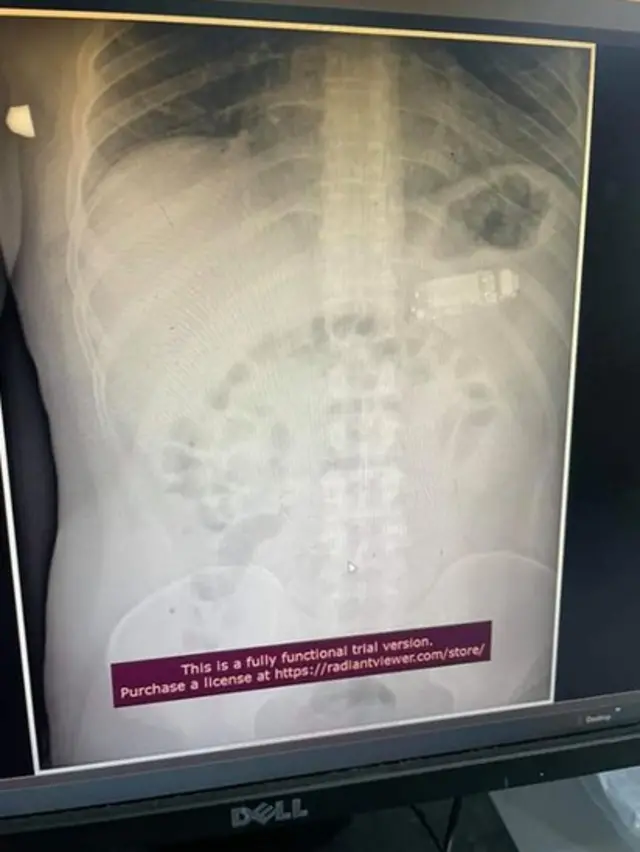

Tako je nedavno u Prištini lekare posle rentgena sačekalo iznenađenje - na snimku se videlo da je tridesettrogodišnji muškarac progutao mobilni telefon.

Doktor Skender Teljaku, internista i gastroenterolog koji je bio zadužen za endoskopsko izvlačenje predmeta iz pacijenta, kaže da se telefon podelio na tri dela.

„Prvo smo izvadili plastični deo - maskicu koja se odvojila, potom ostatak telefona, a na kraju bateriju", kaže on za BBC na srpskom.

Zahvat je trajao duže od dva sata.

„Bilo je previše sluzi u stomaku, nisam mogao da uhvatim delove.

„Teško je da se delovi telefona zakače za instrumente u takvoj okolini", kaže.

Mučili su se i više puta pokušavali da izvuku strano telo.

Neki ljudi nisu verovali da je Teljakuov tim izvadio telefon.

„Komentarisali su da smo lepili pacijentu telefon za leđa kad smo radili rentgen.

„Nije im palo na pamet da je namerno progutao", navodi.